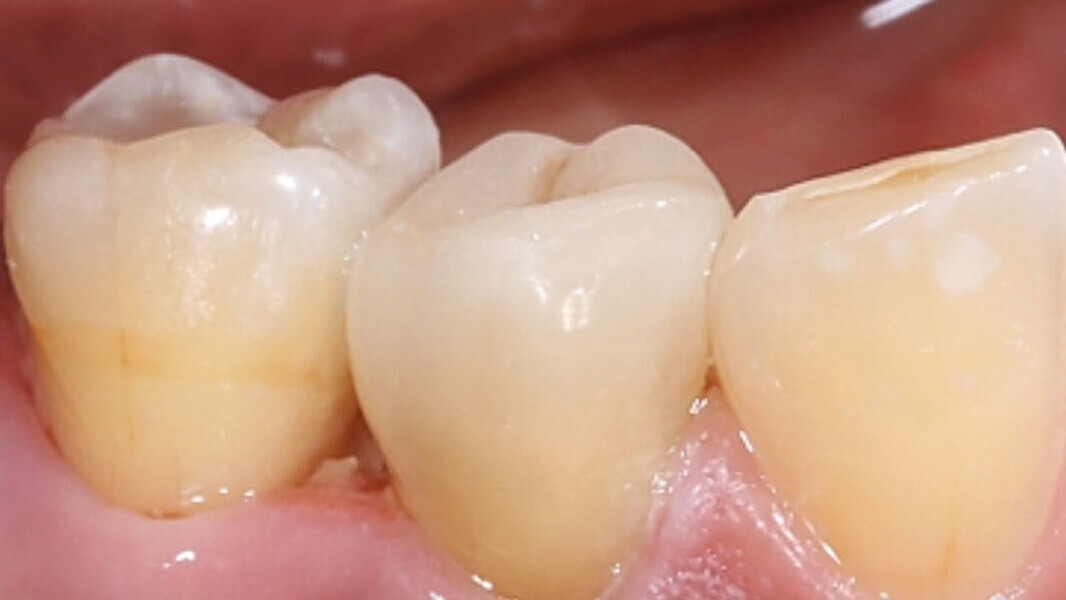

Fig. 2. Estado tras la revisión, la colocación de la espiga y la reconstrucción.

Fig. 3. Durante la preparación se procuró no dejar ningún borde afilado en la cavidad.

Fig. 4. Únicamente se acortaron por oclusal las paredes remanentes de la cavidad.